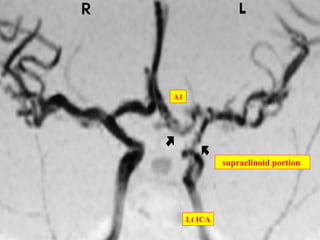

supraclinoid portion

A1

Lt ICA

• #24 left internal carotid artery and its branches. The arrow on the right points to the supraclinoid portion of the internal carotid. The arrow on the left points to the horizonal section of the anterior cerebral artery.